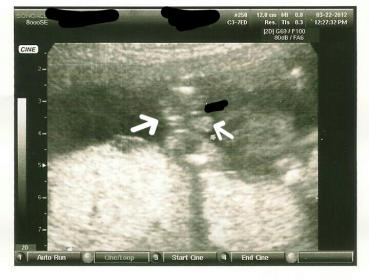

So I know its a boy just wonderig what and why those three lines under the scrotum are there. Any answers? Thanks.

The second picture has an arrow pointing between the legs. I should have asked my ob but he was going so fast I didn't notice the lines until I got home.

Attachment 1818There is no penis only scrotum, the 3 lines are under the scrotum on babies butt that is why im confused, I see a scrotum but no penis. I pointed out what lines I am talking about so no one ilgets confused.